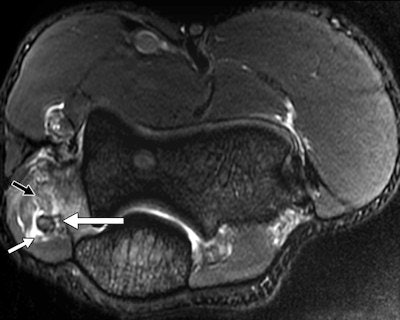

A 30-year-old male judo athlete with valgus stress and hyperextension injury of elbow. Top: Coronal proton density-weighted fat-saturated MRI shows full-thickness tear (white arrow) of proximal humeral attachment of anterior bundle of ulnar collateral ligament (UCL) and edema (black arrow) within surrounding muscle fibers. Below: Axial proton density-weighted fat-saturated MRI shows UCL posterior bundle disruption (long white arrow), with fluid surrounding ulnar nerve (short white arrow). However, ulnar nerve was contiguous on sequential images, with no transection. High-grade tear of flexor carpi ulnaris (black arrow) also was seen. Bottom: Axial proton density-weighted fat-saturated MRI shows high-grade tear of flexor digitorum superficialis (long arrow) and fluid surrounding median nerve (short arrow). All images reprinted with permission from the American Journal of Roentgenology.